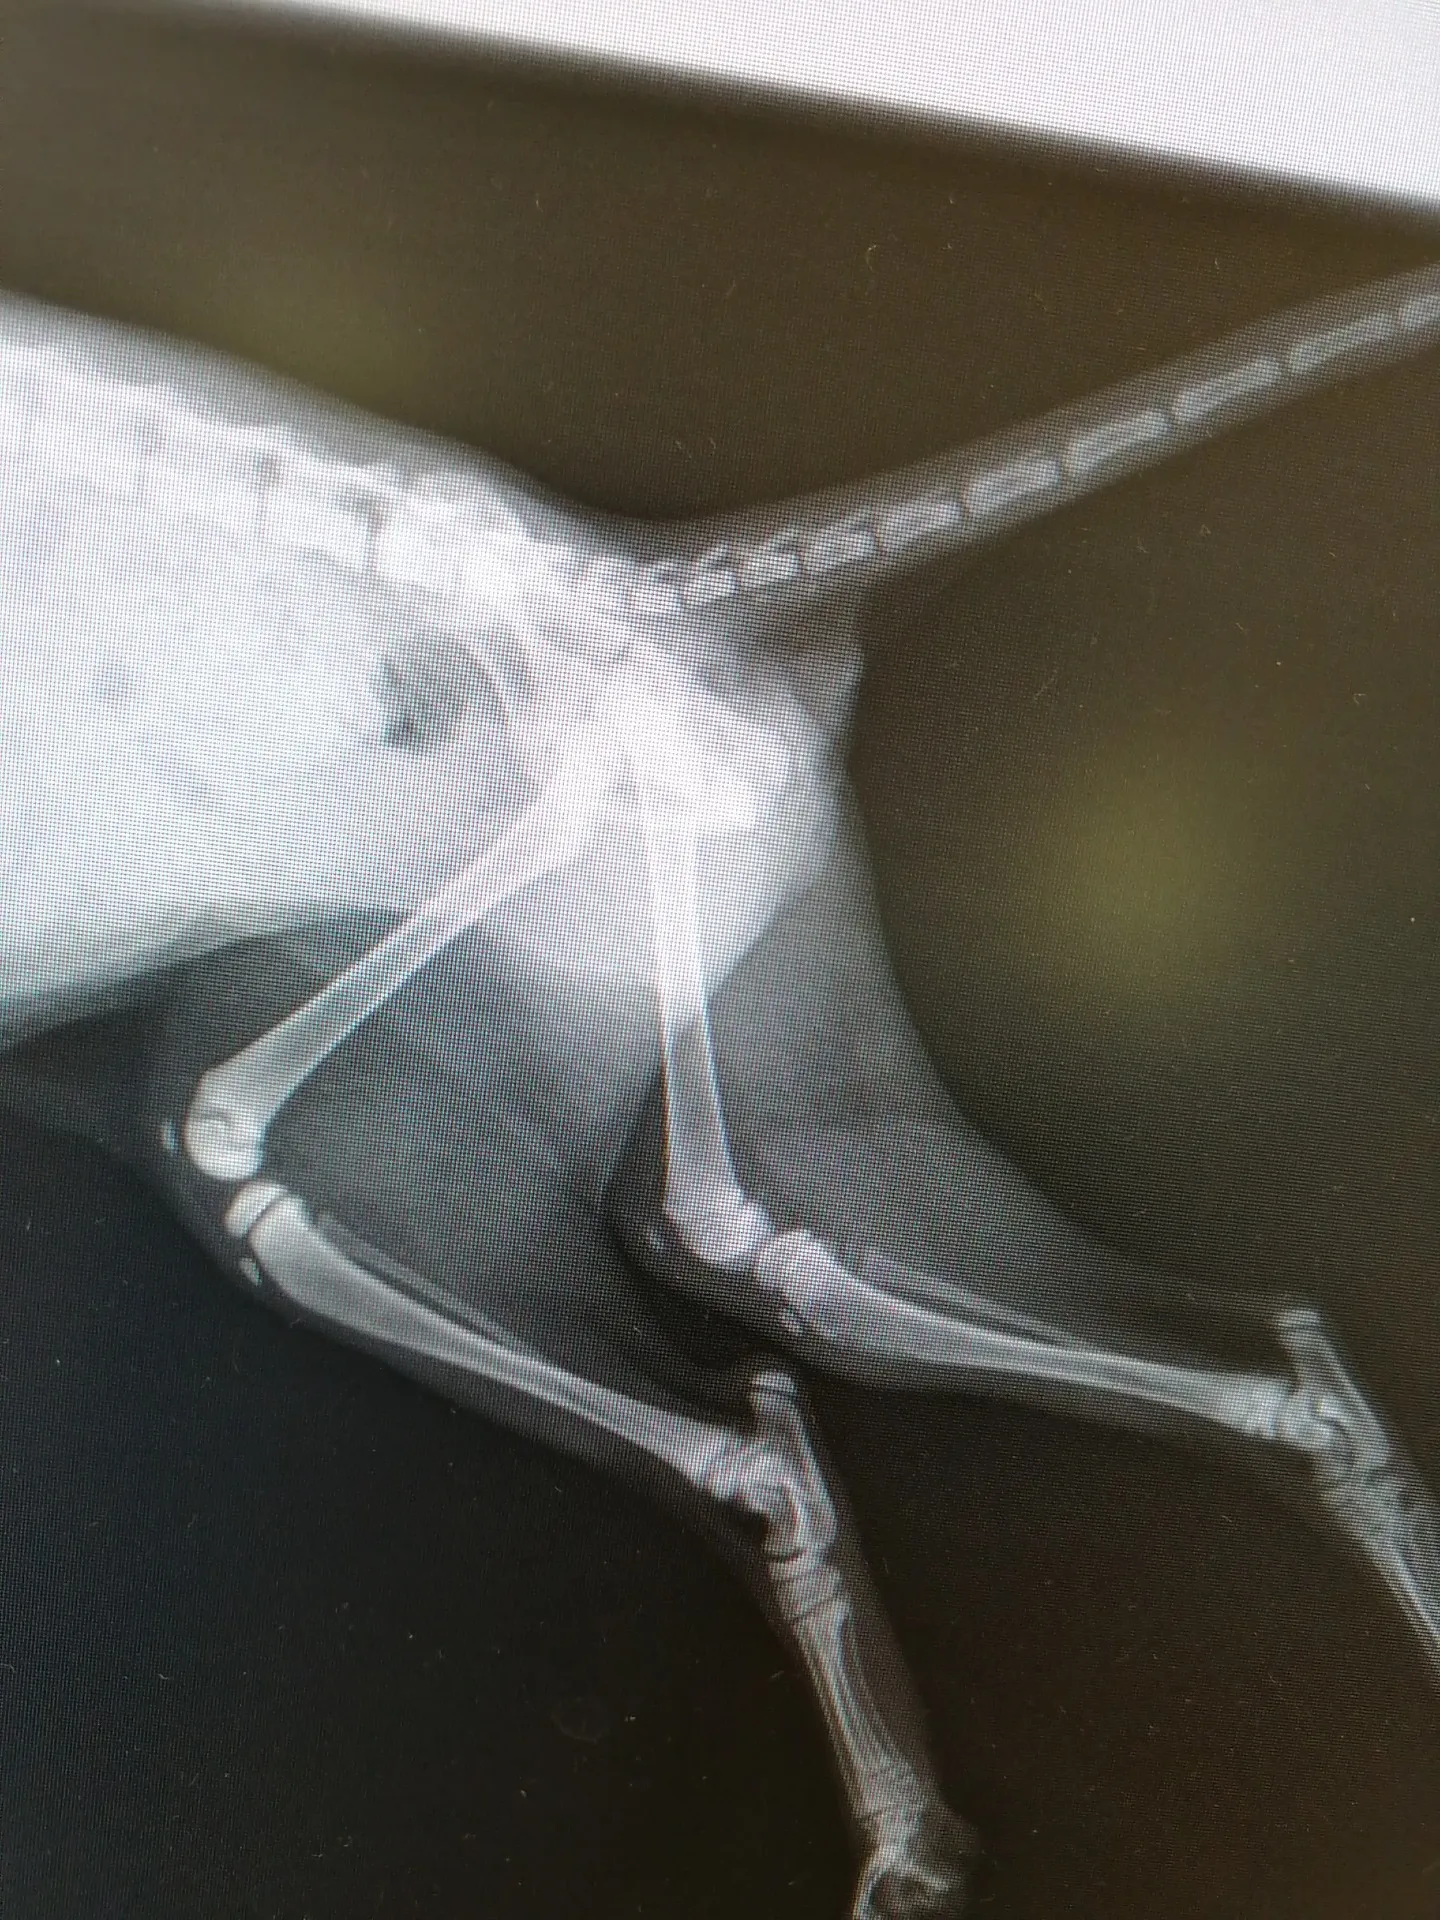

レントゲンの結果が出ました。

左後脚、骨と骨の間に隙間があり、開いていて右脚と比べると明らかな違いがあります。

歩き方がおかしいのはその隙間幅が原因でした。

では、何故そうなっているのか、異骨の原因は?

と尋ねる私に、現時点の資料と見解では確定できないけど、仔猫すぎるため特化した治療ができない事、急な治療が必要な状態ではない事が告げられ、サプリメントを服用しながら成長過程を見ていく事になりました。